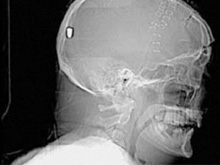

В Британии врачи нашли у пациента пулю в голове

Фото новостиВ Британии у пациента, который поступил в клинику с подозрением на инсульт, врачи обнаружили пулю в голове. Но остается неизвестным, как мужчина получил ранение.

Рентгеновские снимки головы показали, что в полости черепа находится инородный предмет. Мужчине сделали томографию головы, и врачи установили, что этим предметом является пуля.

Эксперты по баллистике, изучив снимки пациента, пришли к выводу, что пуля, застрявшая в затылочной области, могла попасть туда через глаз. Но мужчина не помнит, что именно с ним произошло.

Врачи попытались удалить пулю, однако это оказалось невозможным из-за ее положения по отношению к окружающим структурам. Пациент остается в больнице, а его состояние расценивается как стабильное.